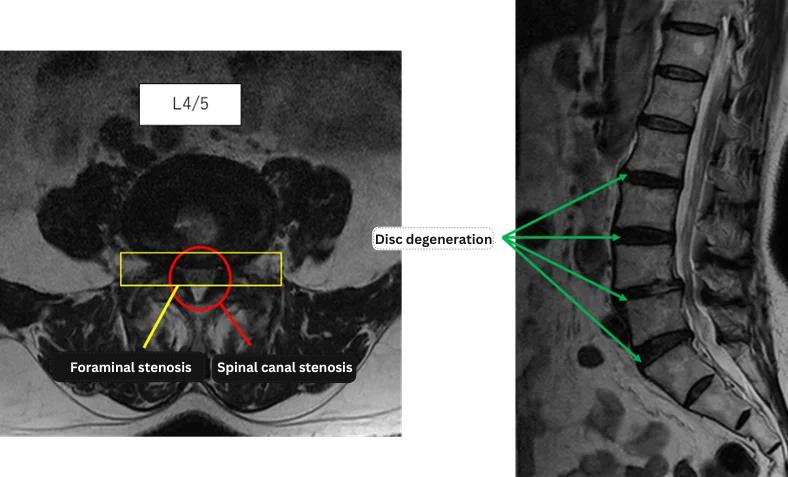

L1/2: No abnormalities

L2/3: Disc degeneration

L3/4: Disc degeneration

L4/5: Spinal canal stenosis, bilateral foraminal stenosis, disc degeneration

L5/S: Disc degeneration

The above findings were also observed on the imaging.

Spinal canal stenosis, disc degeneration, and foraminal stenosis at L3/4, L4/5, and L5/S are considered the most likely causes of the patient’s primary symptoms.